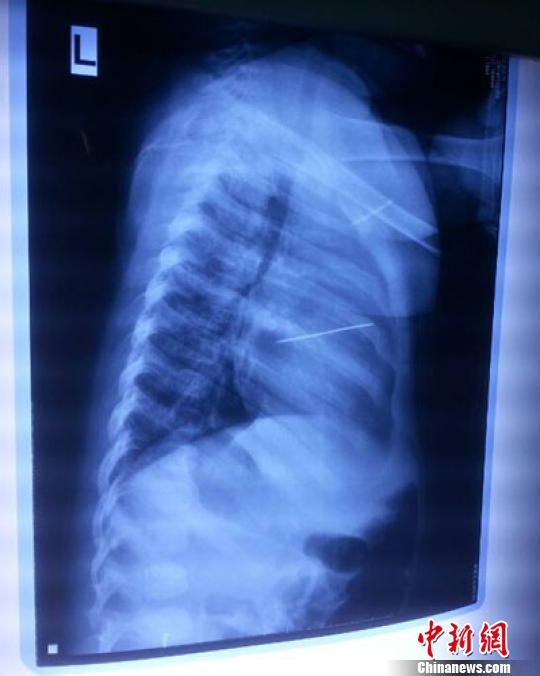

女嬰胸片提示心臟里面扎了一個縫衣針 蔡迅翔 攝

醫(yī)院胸心外科主任翟波介紹說,1月22日,小患者彤彤因為發(fā)燒抽搐來醫(yī)院就診,常規(guī)檢查時發(fā)現(xiàn)孩子心臟里面扎了一個縫衣針。

“第二天上午,我們做了個緊急彩超檢查,發(fā)現(xiàn)針是從患者右心室表面刺入,穿破室間隔,到達左心房,中間還有一部分損害到二尖瓣。于23號下午,我們就做了一個緊急手術(shù),手術(shù)中發(fā)現(xiàn),這枚針已經(jīng)刺入心臟,沒入了右心室的下面,表面已經(jīng)看不到針了,僅能看到一個小針眼,還在往外滲血,一點一點的滲,心包腔里面大概有100多毫升的出血,心包上一個洞,針在右心室表面刺入以后,穿過室間隔,在二尖瓣的上方,進入了左心房,在針的四周,有很多纖維沉積物,包繞著這枚針?!钡圆ㄕf,他們把針取出來以后,測量了一下,長度大概是五厘米,同時發(fā)現(xiàn)這個針給患者左心房的后壁造成了一定的損傷,左心房的后壁已經(jīng)損傷了三分之二,還剩下有左心房的外膜,很薄的一層,如果這一層再破的話,這個孩子將會引起大出血,很快就會死亡。